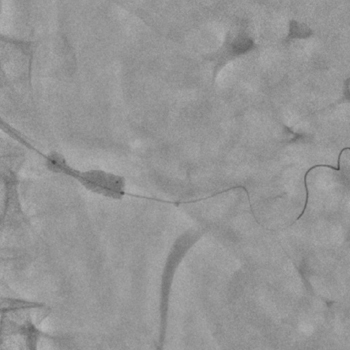

Бифуркационное стентирование почечной артерии

Ангиографическое исследование аорты и селективная ангиография сосудов почек выявило критический стеноз a. segmenti inferioris и короткую a. renalis sinistra

Операторы: Андрей Мальцев, Дмитрий Лебедев